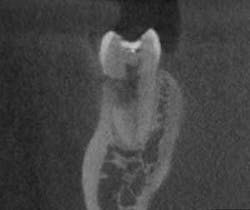

- In Figure 8, the lesion is advanced significantly (one-and-a-half years had gone by) the irregular borders and moth-eaten appearance is easily observed.

- Definitive diagnosis: external resorption.